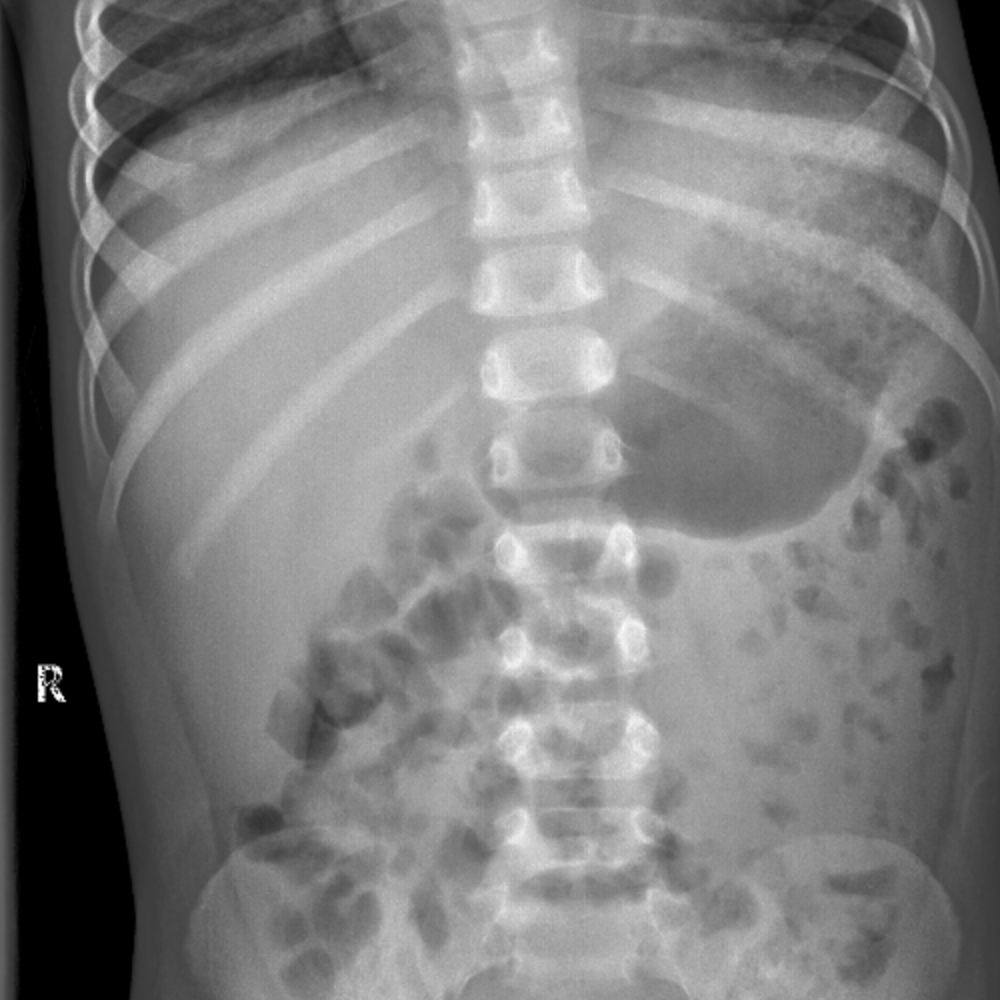

Extends to the hemidiaphragm; Although ultrasound and CT are more informative means of imaging the solid organs of the abdomen, occasionally you will see evidence of enlarged organs on an abdominal Xray Hepatomegaly Hover on/off image to show/hide findingsTalk to our Chatbot to narrow down your search

Hepatomegaly & Transient Hepatomegaly & XRay Abnormal Symptom Checker Possible causes include Hepatopathy Check the full list of possible causes and conditions now!Talk to our Chatbot to narrow down your searchAssessment of liver size is commonly made on ultrasound or CT, although gross hepatomegaly may be apparent on abdominal radiograph For the adult liver midclavicular line averages cm in craniocaudal length 2 a liver that is longer than cm in the midclavicular line (MCL) is considered enlarged

Psoas muscle symmetrical triangles either side of the lumbar spine Hepatomegaly can represent intrinsic liver disease or may be the presenting physical finding of a generalized disorder Early diagnosis and treatment of children who have liver disease is important because specific treatments are available for some diseases that can prevent disease progression or hepatic failureHepatomegaly is another word to describe this problem If both the liver and spleen are enlarged, it is called hepatosplenomegaly Abdominal xray;

Hepatomegaly is the condition of having an enlarged liver It is a nonspecific medical sign having many causes, which can broadly be broken down into infection, hepatic tumours, or metabolic disorder Often, hepatomegaly will present as an abdominal mass Depending on the cause, it may sometimes present along with jaundiceHepatomegaly (abdominal xray) Case contributed by Dr Jeremy Jones Diagnosis probable Diagnosis probable From the case Hepatomegaly (abdominal xray) Xray Loading Stack 0 images remainingSplenomegaly is a subjective radiograph finding as there are no reliable objective criteria;